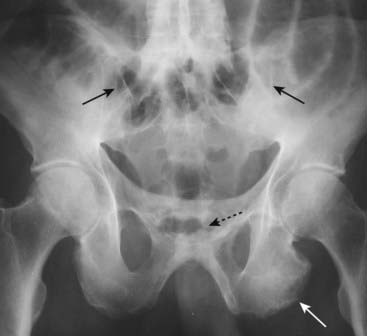

Figure 23-19 Ankylosing spondylitis.

Ankylosing spondylitis is an enthesopathy, a process that produces inflammation with subsequent calcification and ossification at and around the entheses, which are the insertion sites of tendons, ligaments, and joint capsules (solid white arrow points to bony overgrowth at the ischial tuberosity). Bilaterally symmetrical sacroiliitis is the hallmark of ankylosing spondylitis. This eventually leads to bony fusion or ankylosis of the SI joints until they disappear as joints altogether (solid black arrows). The symphysis pubis is also ankylosed (dotted black arrow).